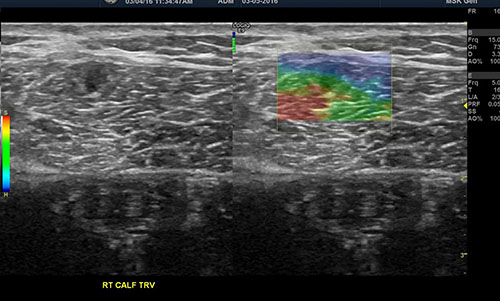

Color Sonoelastography

The most recent advancement in ultrasound technology is color “elastography”—also known as “sonoelastography.” “Sono” is another term for ultrasound, and “elastography” describes the elasticity or density, measured as “hardness” or “softness”, of tissue.[11] Ultrasound elastography has been used for many years to help doctors in diagnosing tumors since tumors are harder than the surrounding tissue. In the last several years, it has emerged as a useful tool in musculoskeletal medicine as another potential diagnostic tool to help detect early or small ligament, tendon, and muscle tears and weaknesses which would not otherwise be easily seen via either MRI or greyscale ultrasound. Color sonoelastography can also be used to help monitor improving tissue density over a course of treatment. There is a scale of tissue “softness” to “hardness” which shows up in colors ranging from red to blue. Tears show up as “softer” simply because the tissue is weaker and less dense than the surrounding stronger, “harder,” healthy tissue.

Sonoelastogram showing a small muscle tear

Figure 1: Sonoelastogram showing a small muscle tear which did not show up in MRI or regular greyscale ultrasound. [Note the muscle tear (red area) seen on the right (color) side. This is an image done on a 20-year-old runner who had persistent calf pain with activity. PRP Prolotherapy directed to the tear (red area) resolved this patient’s pain.]